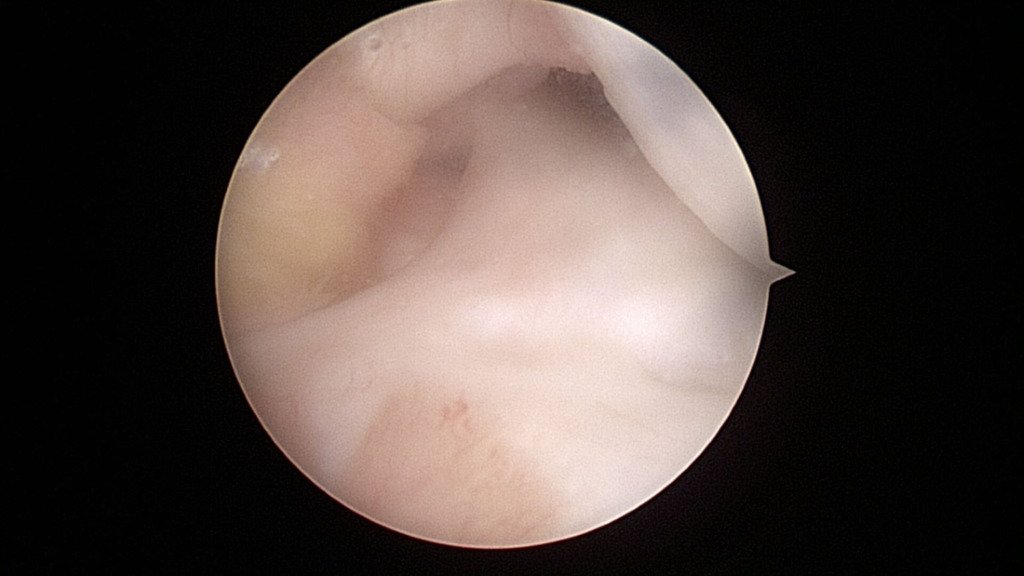

The anterior and posterior roots of the lateral meniscus were intact (Figure 7).

The lateral meniscal tissue appeared hypertrophied and was noted to be a Wrisberg-type discoid variant (Figure 8).